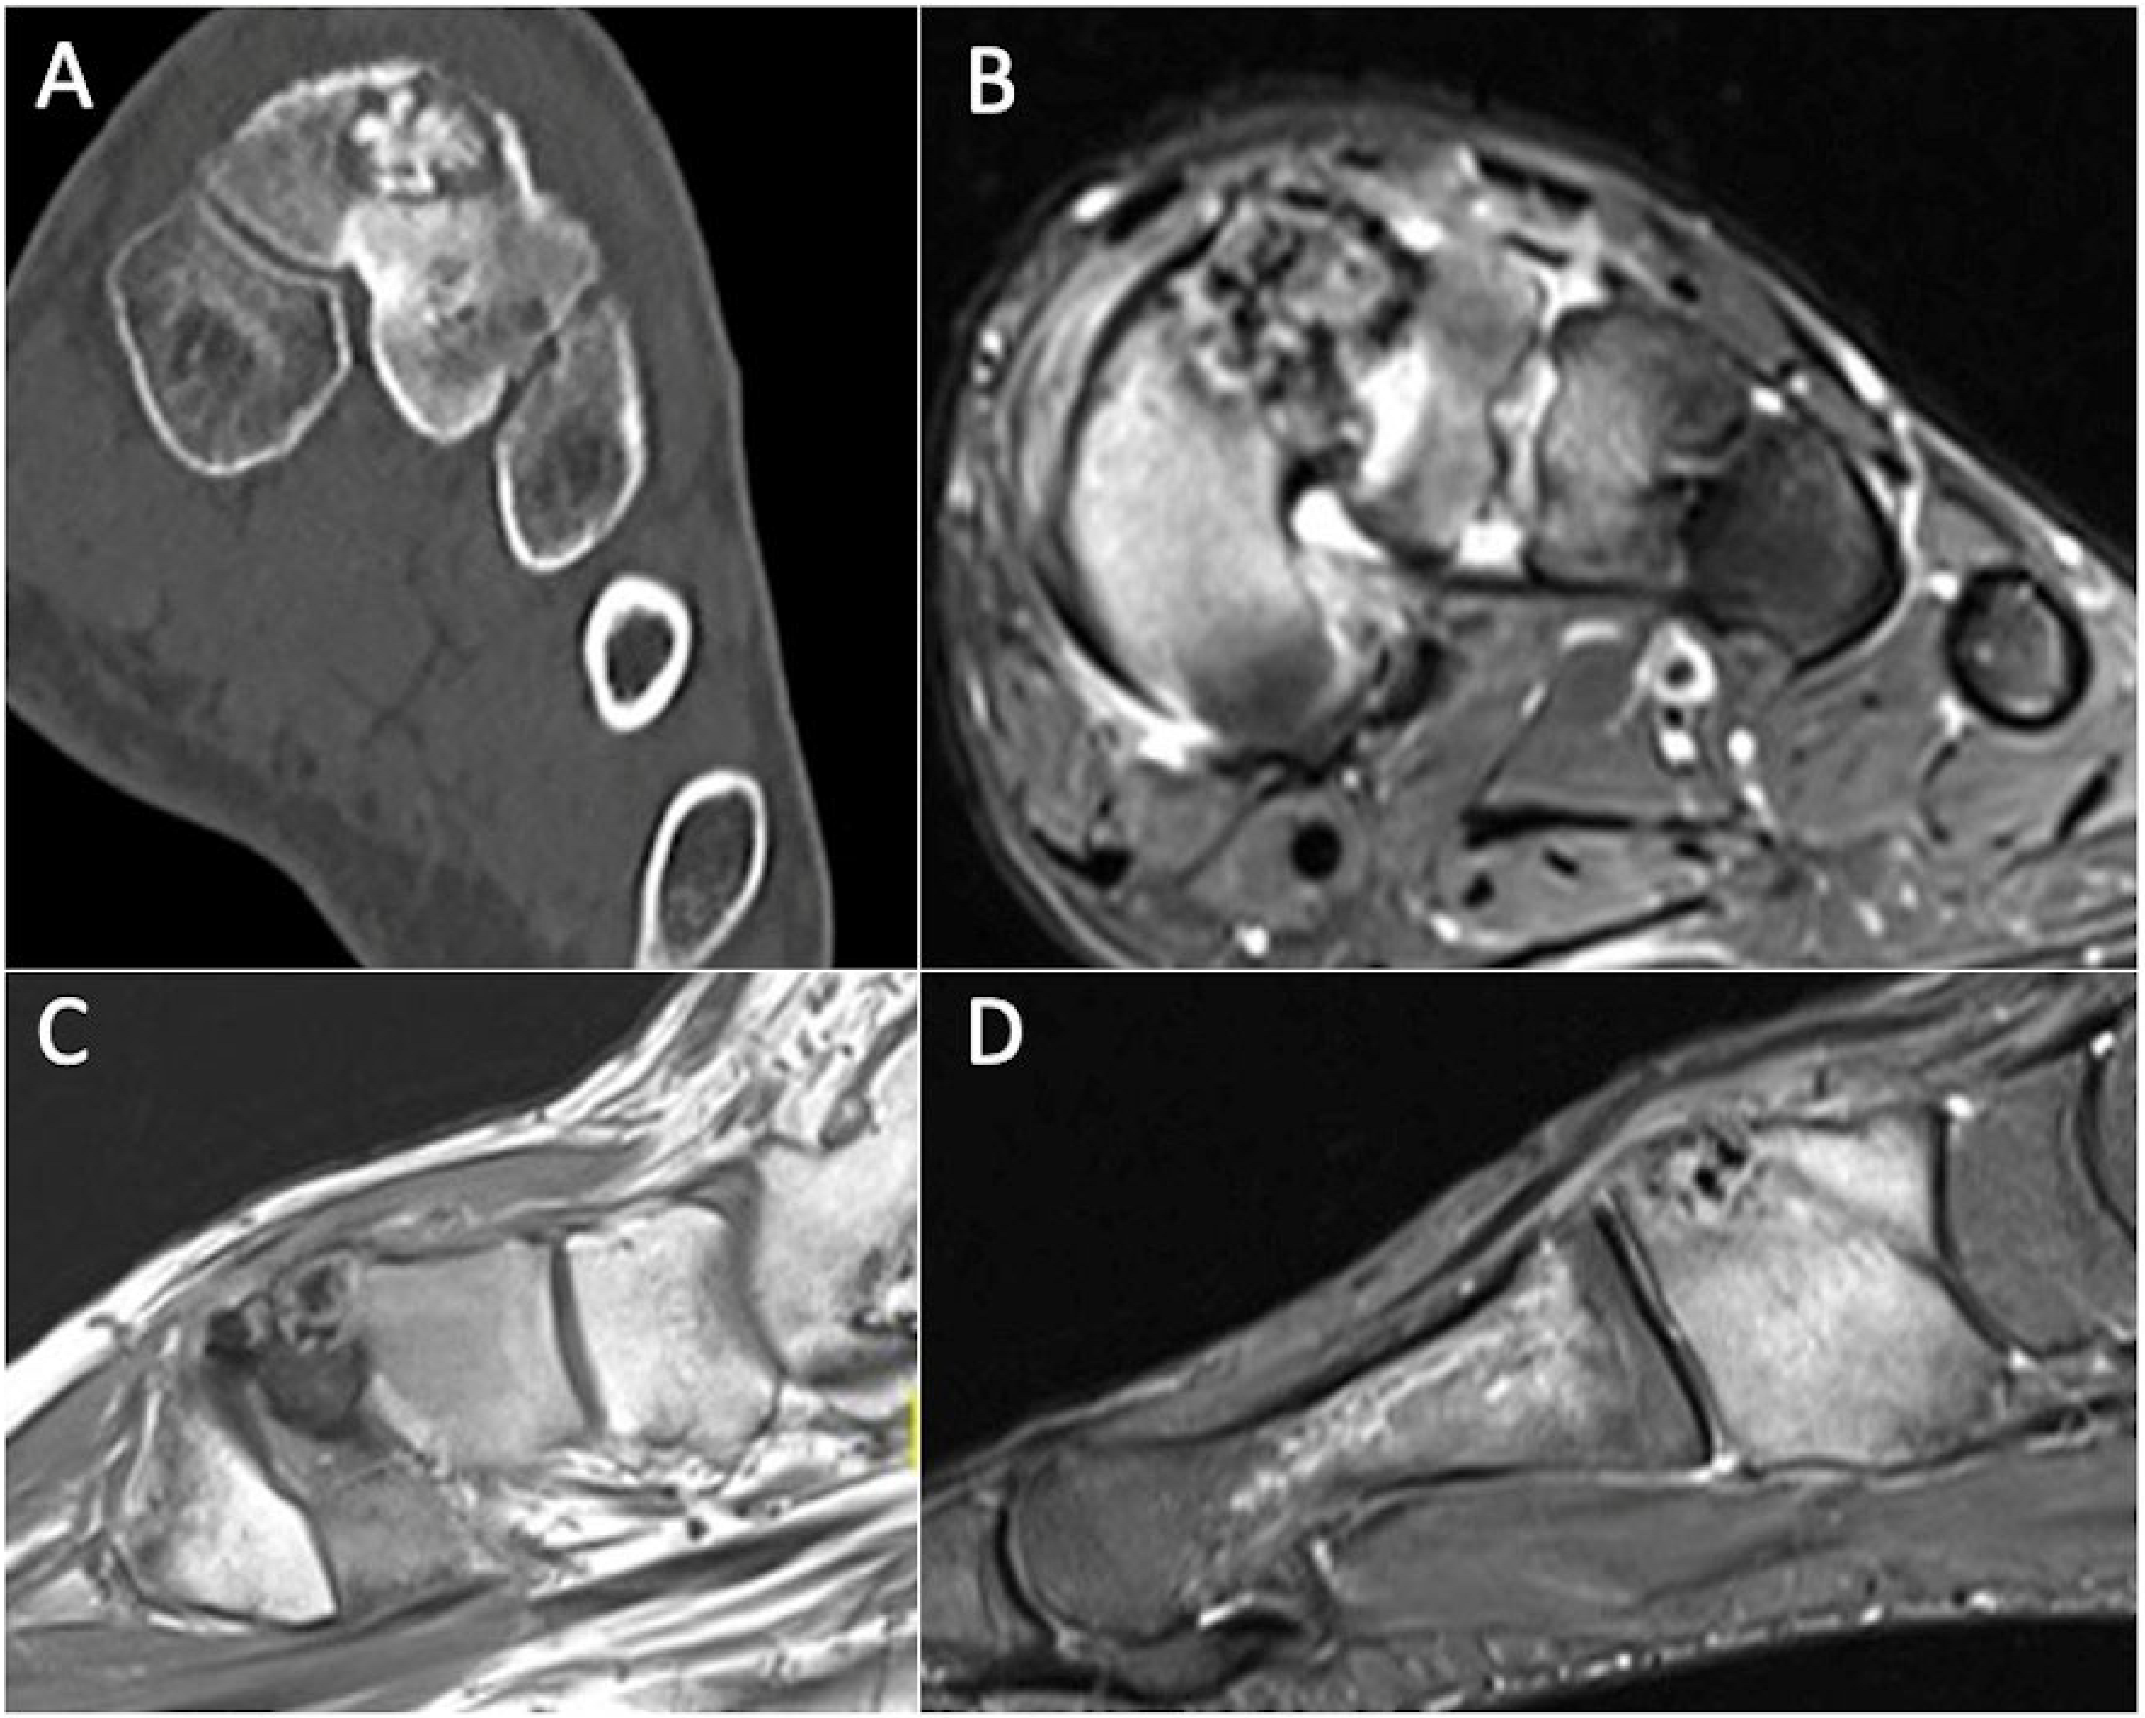

5.3. Osteoblastoma

- Agarwal, S.; Singh, D.K.; Rustagi, A.; Krishna, L.; Talwar, J. Osteoblastoma of Talus: A Diagnostic Dilemma. Cureus 2020, 12, e11838. [Google Scholar] [CrossRef]

- Kroon, H.M.; Schurmans, J. Osteoblastoma: Clinical and radiologic findings in 98 new cases. Radiology 1990, 175, 783–790. [Google Scholar] [CrossRef]